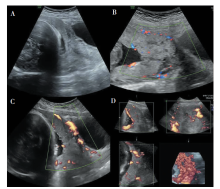

SUN Tiantian, YE Baoying, YANG Yu, NIU Jianmei. Color Doppler ultrasound and magnetic resonance imaging in prenatal diagnosis of pernicious placenta previa and pernicious placenta previa with placenta accreta: clinic value and analysis of missed diagnosis[J]. Journal of Diagnostics Concepts & Practice, 2021, 20(02): 173-177.